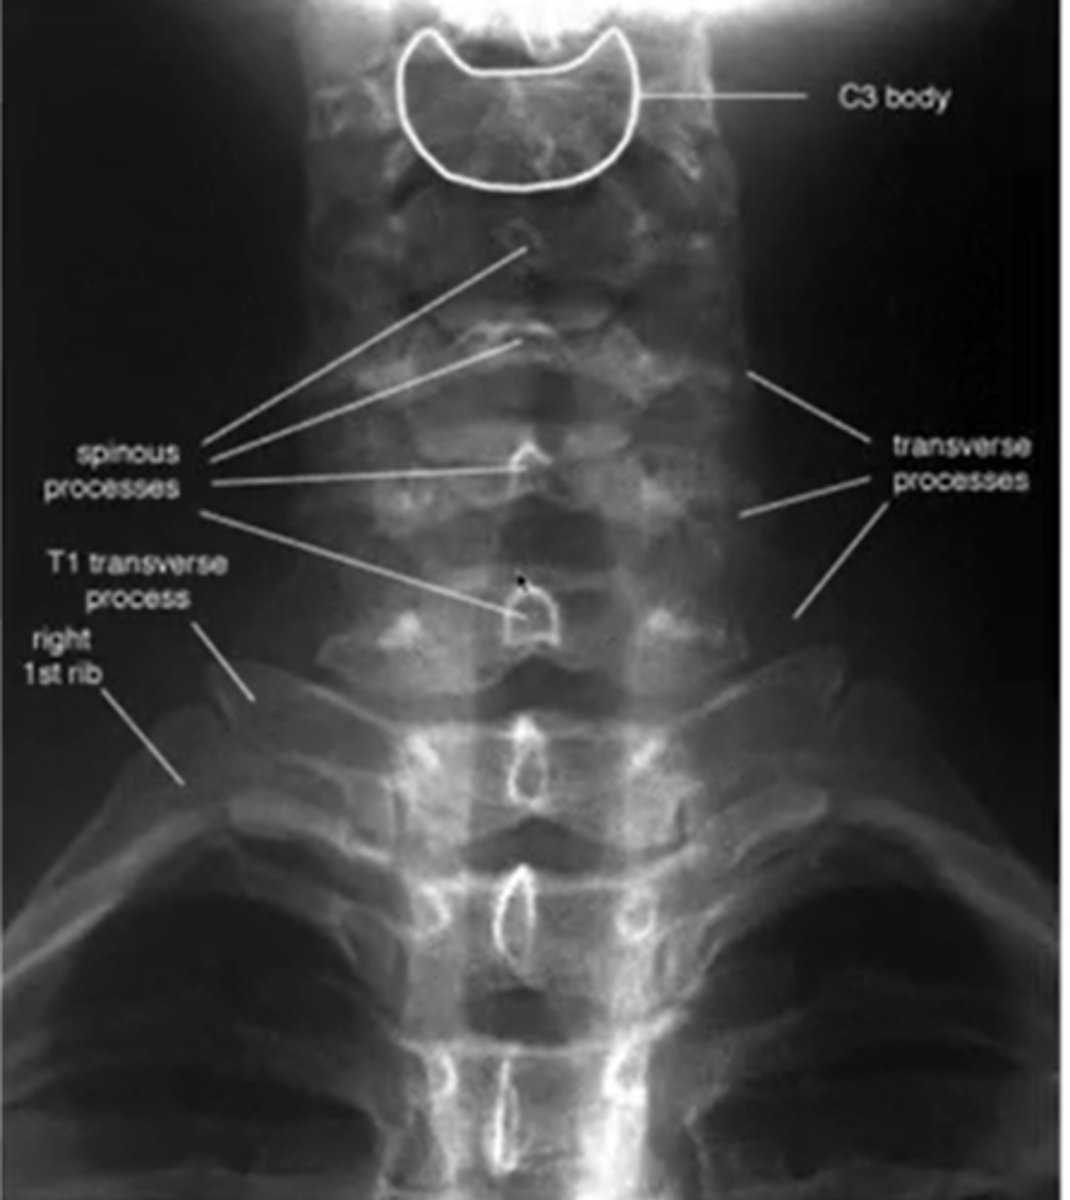

at what angle is the ap cs taken?

15-20 deg

what does a normal AP cs look like

what view of the c/s can you see the pedicles?

AP

what are you looking for during AP view of CS